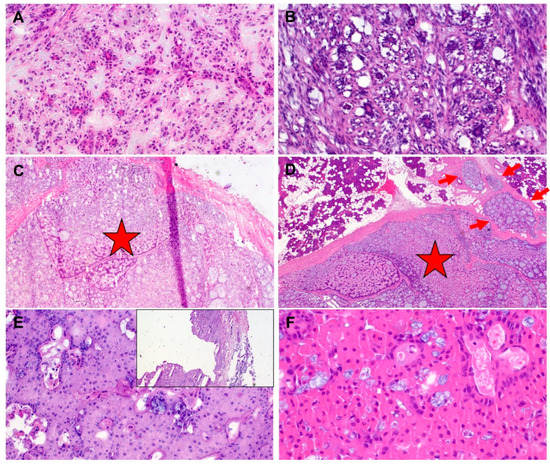

| Case Number | Frozen Section Diagnosis | Definitive Diagnosis | Pathologist | Impact on Management | Source/Type of Error |

|---|---|---|---|---|---|

| 1 | Cystadenolymphoma | G1 mucoepidermoid carcinoma | B | Revision surgery | Interpretative |

| 2 | “No malignancy” | Acinic cell carcinoma | B | Revision surgery | Interpretative |

| 3 | Pleomorphic adenoma | Basal cell carcinoma ex pleomorphic adenoma | B | No revision surgery (on patient’s request) | Sampling |

| 4 | Pleomorphic adenoma | Acinic cell carcinoma | B | Revision surgery | Interpretative |

| 5 | “No malignancy” | Acinic cell carcinoma | B | No revision surgery (multiple co-morbidities) | Interpretative |

| 6 | “No malignancy” | G1 mucoepidermoid carcinoma | B | Revision surgery | Interpretative |

| 7 | Pleomorphic adenoma | Low-grade adenocarcinoma ex pleomorphic adenoma | B | Revision surgery | Sampling |

| 8 | Basal cell adenoma | Adenoid cystic carcinoma | B | No revision surgery (complete parotidectomy already performed) | Interpretative |

| 9 | Pleomorphic adenoma | Myoepithelial carcinoma ex pleomorphic adenoma | B | Revision surgery | Interpretative |

| 10 | Pleomorphic adenoma | Ductal adenocarcinoma ex pleomorphic adenoma | A | Revision surgery | Sampling |

| 11 | Pleomorphic adenoma | Epithelial myoepithelial carcinoma | B | Revision surgery | Interpretative |

| 12 | Basal cell adenoma | Epithelial myoepithelial carcinoma | A | No revision surgery (subtotal parotidectomy already performed) | Interpretative |

| 13 | “No malignancy” | G1 mucoepidermoid carcinoma | B | No revision surgery (multiple co-morbidities) | Interpretative |

| 14 | Basal cell adenoma vs. pleomorphic adenoma, “no malignancy” | Secretory carcinoma | B | Tumour in accessory gland, revision surgery not required | Interpretative |

| 15 | Pleomorphic adenoma | Adenoid cystic carcinoma | B | Revision surgery | Interpretative |

| 16 | Oncocytic adenoma | G1 mucoepidermoid carcinoma | B | Revision surgery | Interpretative |